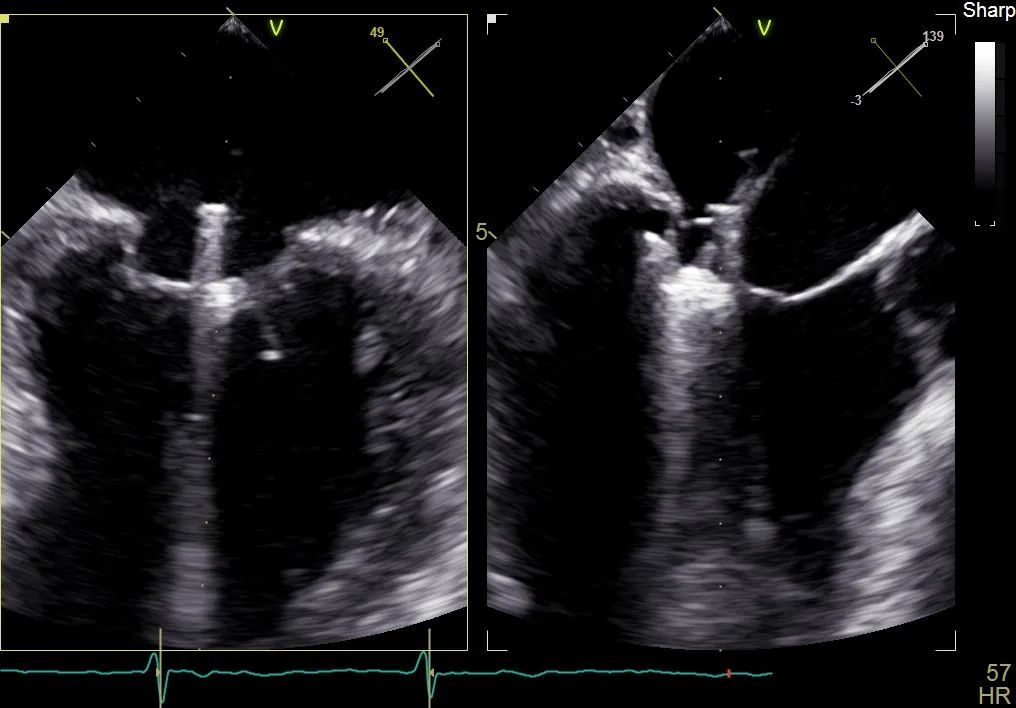

术前行经食道超声评估:继发性二尖瓣反流,反流程度4+;二尖瓣有效反流口面积(EROA) 0.81 cm²,缩流颈宽度18 mm,反流容积112.36ml,二尖瓣瓣口面积5.06 cm²,平均跨瓣压差5 mmHg,二尖瓣前叶(A2)长度15mm,二尖瓣后叶(P2)长度9 mm;左房内径54mm,左室收缩末期内径50mm,左室射血分数43%,肺动脉压83 mmHg。

术前食道超声可见二尖瓣重度反流,前后叶对合不全伴有间隙,且反流束宽度18mm

再次反复测试第二枚二尖瓣钳夹的稳定性,超声复查提示二尖瓣反流明显改善,平均跨瓣压差4 mmHg